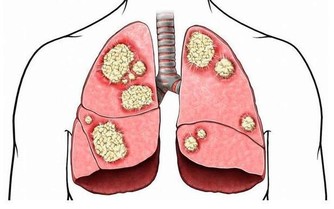

根據衛福部公布的民國103年十大死因,癌症連續33年蟬聯榜首,

占約所有死亡人數3成,平均每11分24秒就有一人死於癌症。

其實癌症發生的主要原因在於我們把食物吃下肚後無法排出體外的殘留物質,

這些老廢物質一旦堆積久了酸化後產生活性氧物質,便引發各種疾病。

卻有抗酸化、抑制癌細胞增殖、致癌物質無毒化、強化免疫力等功效,

免於身體受到體內毒素的侵害,除了能防癌外,